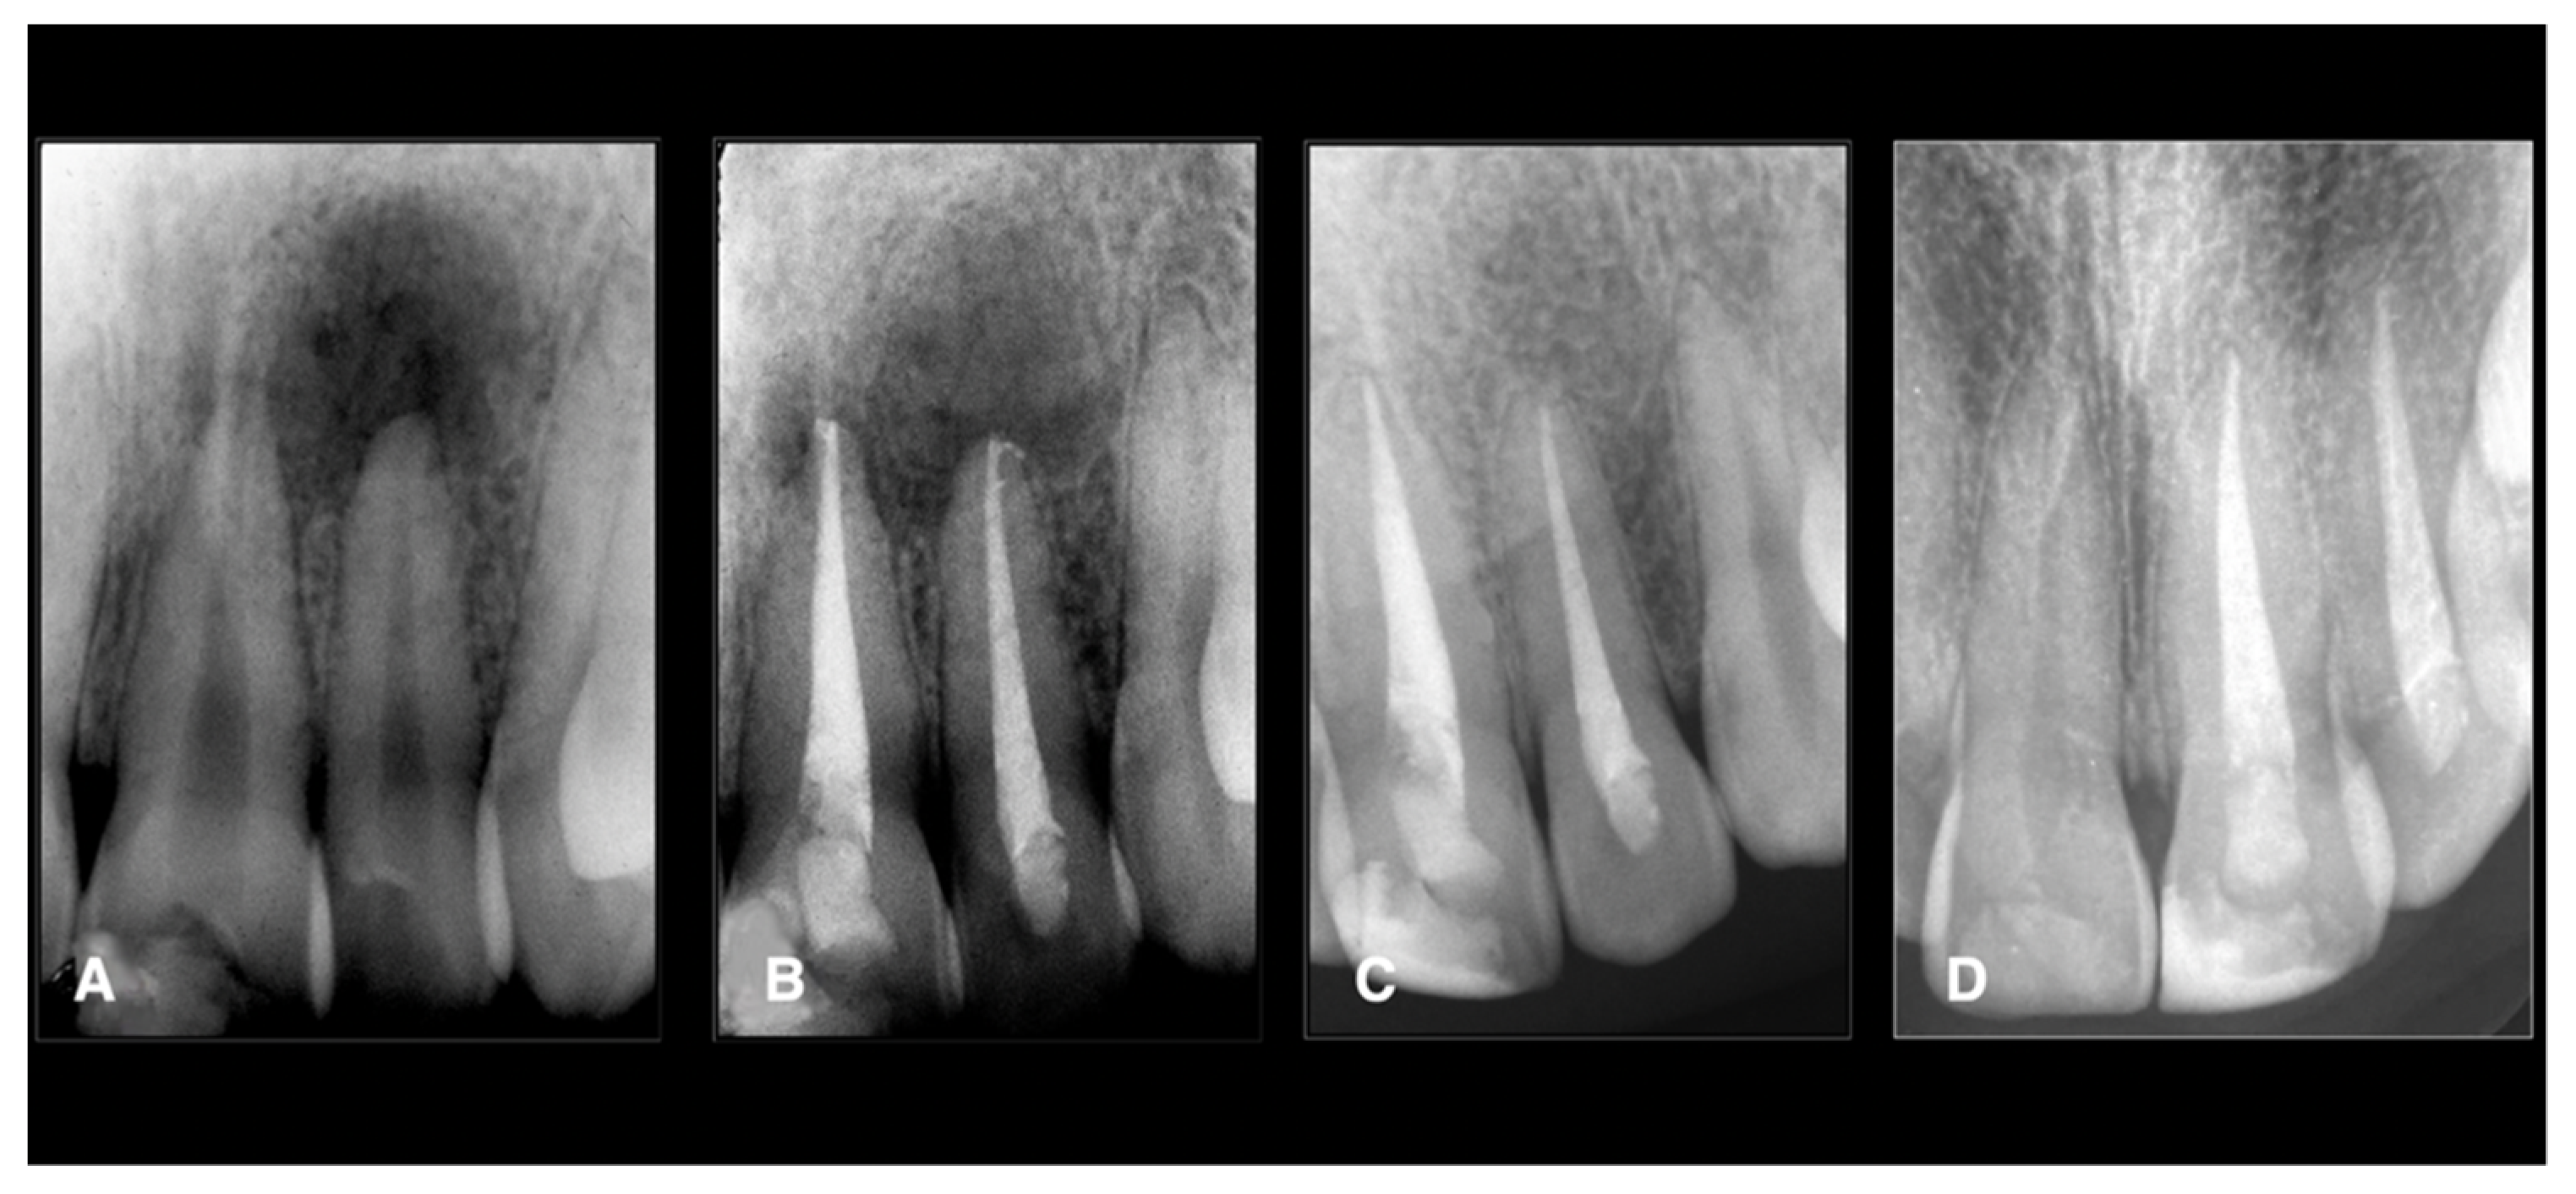

| All data Male: 55 Female: 35 Age: all the patients were between 20 and 45 years. Oral hygiene: 65 patients had good hygiene. Tobacco use: 10 patients used it. Teeth: 20 maxillary molars, 40 mandibular molars, 30 maxillary premolars. Intraoperative data collection Twenty teeth had sealer extrusions. The working length was respected in all teeth. Postoperative data collection Post-treatment symptoms were assessed two days after the treatment using a visual analogue scale (VAS; 0 and 10) Thirteen maxillary molars: 2 Seven maxillary molars: 1 Five mandibular molars: 4 Eighteen mandibular molars: 3 Ten mandibular molars: 2 Seven mandibular molars: 1 Sixteen maxillary premolars: 2 Twelve maxillary premolars: 1 Two maxillary premolars: 3 Total number: 90 teeth Two patients (2 teeth) did not come for the follow-up. Of the 88 teeth, 84 (95%) were healed, and four (5%) failed. Four teeth failed: 2 maxillary premolars and two mandibular molars (these teeth did not have sealer extrusion). One maxillary premolar failed with vertical root fracture. |

| Follow-up n = 88 | 84; 95.4 | 0; 0.0 | 0; 0.0 | 84 95.4 | 4; 4.6 | 0; 0.0 | 4; 4.6 |